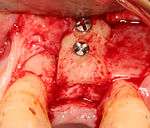

- Placement of the implant: The implant screw is placed and can be self-tapping,[18](pp100–102) otherwise the prepared site is tapped with an implant analog. It is then screwed into place with a torque controlled wrench[19] at a precise torque so as not to overload the surrounding bone (overloaded bone can die, a condition called osteonecrosis, which may lead to failure of the implant to fully integrate or bond with the jawbone).

- Tissue adaptation: The gingiva is adapted around the entire implant to provide a thick band of healthy tissue around the healing abutment. In contrast, an implant can be "buried", where the top of the implant is sealed with a cover screw and the tissue is closed to completely cover it. A second procedure would then be required to uncover the implant at a later date.

Immediate placement

An increasingly common strategy to preserve bone and reduce treatment times includes the placement of a dental implant into a recent extraction site. On the one hand, it shortens treatment time and can improve esthetics because the soft tissue envelope is preserved. On the other hand, implants may have a slightly higher rate of initial failure. Conclusions on this topic are difficult to draw, however, because few studies have compared immediate and delayed implants in a scientifically rigorous manner.[20]